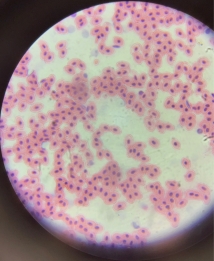

Frog’s Blood